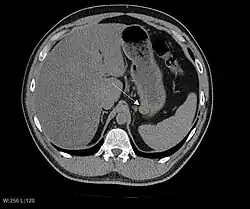

CT scanning is often undertaken (see the radiology section).

The purpose of radiologic imaging is to locate the lesion, evaluate for signs of invasion and detect metastasis. Features of GIST vary depending on tumor size and organ of origin. The diameter can range from a few millimeters to more than 30 cm. Larger tumors usually cause symptoms in contrast to those found incidentally which tend to be smaller and have better prognosis.[4][20] Large tumors tend to exhibit malignant behavior but small GISTs may also demonstrate clinically aggressive behavior.[21]

Barium fluoroscopic examinations and CT are commonly used to evaluate the patient with abdominal complaints. Barium swallow images show abnormalities in 80% of GIST cases.[21] However, some GISTs may be located entirely outside the lumen of the bowel and will not be appreciated with a barium swallow. Even in cases when the barium swallow is abnormal, an MRI or CT scan must follow since it is impossible to evaluate abdominal cavities and other abdominal organs with a barium swallow alone. In a CT scan, abnormalities may be seen in 87% of patients and it should be made with both oral and intravenous contrast.[21] Among imaging studies, MRI has the best tissue contrast, which aids in the identification of masses within the GI tract (intramural masses). Intravenous contrast material is needed to evaluate lesion vascularity.

Preferred imaging modalities in the evaluation of GISTs are CT and MRI,[23]: 20–21 and, in selected situations, endoscopic ultrasound. CT advantages include its ability to demonstrate evidence of nearby organ invasion, ascites, and metastases. The ability of an MRI to produce images in multiple planes is helpful in determining the bowel as the organ of origin (which is difficult when the tumor is very large), facilitating diagnosis.

As the tumor grows it may project outside the bowel (exophytic growth) and/or inside the bowel (intraluminal growth), but they most commonly grow exophytically such that the bulk of the tumor projects into the abdominal cavity. If the tumor outstrips its blood supply, it can necrose internally, creating a central fluid-filled cavity with bleeding and cavitations that can eventually ulcerate and communicate into the lumen of the bowel. In that case, barium swallow may show an air, air-fluid levels or oral contrast media accumulation within these areas.[21][25] Mucosal ulcerations may also be present. In contrast-enhanced CT images, large GISTs appear as heterogeneous masses due to areas of living tumor cells surrounding bleeding, necrosis or cysts, which is radiographically seen as a peripheral enhancement pattern with a low attenuation center.[20] In MRI studies, the degree of necrosis and bleeding affects the signal intensity pattern. Areas of bleeding within the tumor will vary its signal intensity depending on how long ago the bleeding occurred. The solid portions of the tumor are typically low signal intensity on T1-weighted images, are high signal intensity on T2-weighted images and enhanced after administration of gadolinium. Signal-intensity voids are present if there is gas within areas of necrotic tumor.[22][26][27]

Features of malignancy

Malignancy is characterized by local invasion and metastases, usually to the liver, omentum and peritoneum. However, cases of metastases to bone, pleura, lungs and retroperitoneum have been seen. In distinction to gastric adenocarcinoma or gastric/small bowel lymphoma, malignant lymphadenopathy (swollen lymph nodes) is uncommon (<10%) and thus imaging usually shows absence of lymph node enlargement.[20] If metastases are not present, other radiologic features suggesting malignancy include: size (>5 cm), heterogeneous enhancement after contrast administration, and ulcerations.[4][20][28] Also, overtly malignant behavior (in distinction to malignant potential of lesser degree) is less commonly seen in gastric tumors, with a ratio of behaviorally benign to overtly malignant of 3-5:1.[4] Even if radiographic malignant features are present, these findings may also represent other tumors and definitive diagnosis must be made immunochemically.